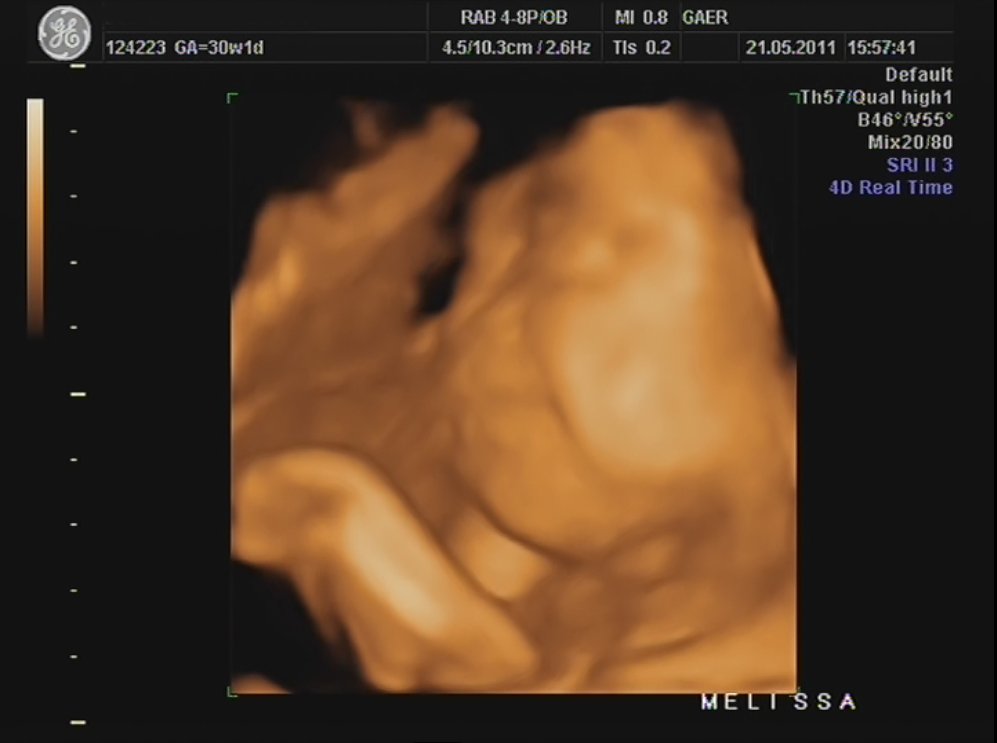

Durante a eco, percebi que a Dra ficou tempo a mais a avaliar o mesmo local e ao fim ela me explicou que viu uma lamina de água a volta do coraçãozinho da minha pricesa.

Ela me explicou que isso acontece a alguns bebés e que não devo me preocupar, que temos que fazer um exame mais detalhado para avaliar o coraçãozinho dela que será feito no Hospital São João e que hoje já trataria de marcar isso...

Quero ser otimista e pensar que a minha princesa está otima mas sabe como é coração de mãe, fica logo apertadinho :(

Estou tão preocupad!!